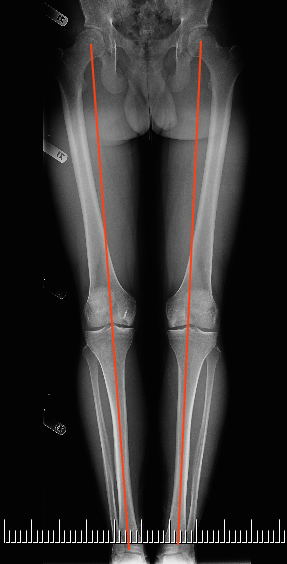

The Art of Limb Alignment, Twelfth Edition: Standard, Shawn。The Art of Limb Alignment | PDF。Amazon.com: The Art of Limb Alignment: Taylor Spatial Frame。。Amazon.com: Visual Perception: A Clinical Orientation, Fifth。Shawn C. Standard 他2名 For more than 30 years, we have taught limb correction surgery at the annual Baltimore Limb Deformity Course (www.DeformityCourse.com). We have used these hands-on experiences with our students to guide us when creating this book. The Art of Limb Alignment is a concise guide for beginners starting on their journey to master the art of limb alignment. Understanding limb alignment and malalignment is a critical task for surgeons who treat lower extremity deformities. The first task is to characterize the deformity: Is the bone angulated? In what direction is the bone angulated? What is the level of the deformity? Where is the apex of the deformity? What is the magnitude of the deformity? Is the bone short? Is it rotated on its axis? All these questions must be answered before correcting the problem. In Chapter 10 of this tenth edition, digital planning software (Bone Ninja app, available as an iPad app teaching tool through the App Store) is used to最新版です。